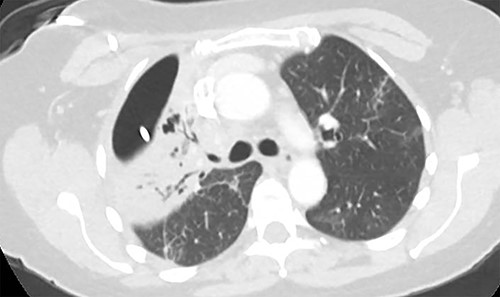

Three weeks following her initial COVID-19 diagnosis, she presented to the hospital with ongoing symptoms and was found to have a right hydropneumothorax and cavitary lesion with parenchymal destruction (Fig. 1). She was treated with broad-spectrum antibiotics and percutaneous chest tube drainage, which showed a continuous one- to two-column air leak. Her pleural fluid grew methicillin-sensitive S. aureus (MSSA). Bronchoscopy revealed mucosal edema and erythema, particularly in the right upper lobe. Despite treatment, she had a persistent air leak, and she was transferred to our facility for further management.

(A) Plain film of chest showing apical hydropneumothorax. (B) Computed tomography axial image demonstrating a complex hydropneumothorax with significant right sided parenchymal infiltrate.